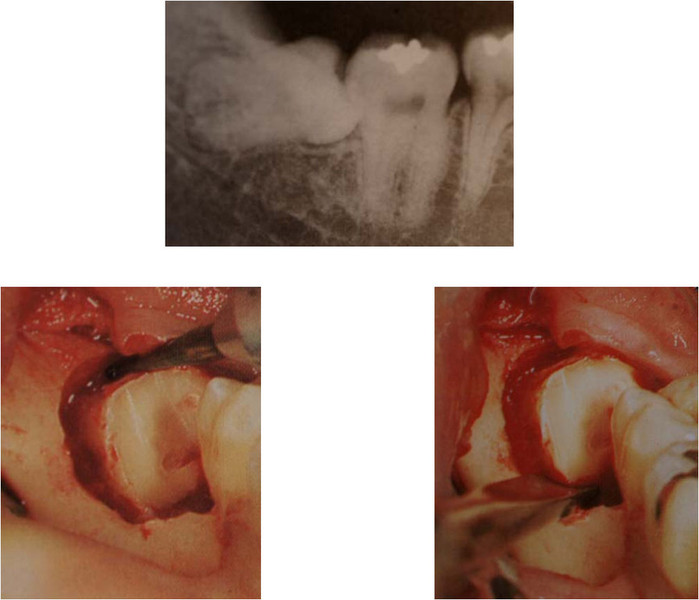

Ottavo con cisti in rapporto a nervo alveolare inferiore

Ottavo inclinato mesialmente con radici ricurve